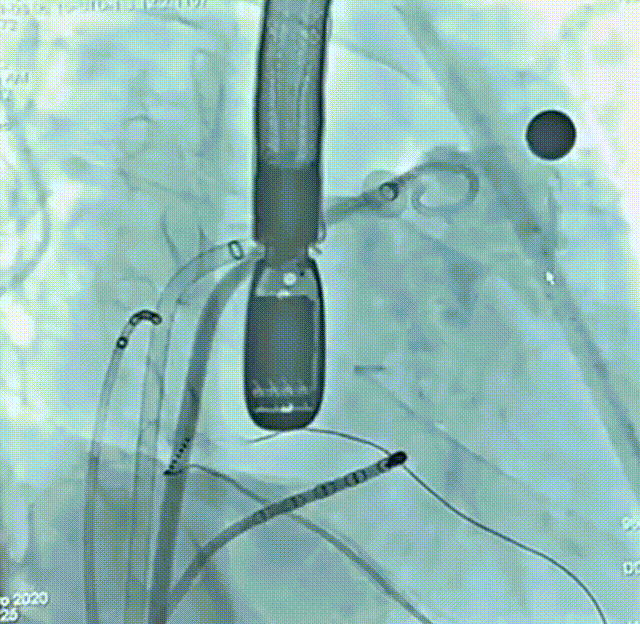

患者为51岁男性,因“反复心悸7-8年”入院,有明确的脑梗死病史,近4年内出现2次脑梗死,右侧肢体存在活动障碍后遗症,考虑由房颤相关血栓栓塞造成。术前动态心电图示心律不齐,房颤律,心脏彩超示左右房内径增大、左室收缩功能减低;房颤CHA?DS?-VASc评分4分、HAS-BLED评分4分,血栓栓塞及出血风险均较高;食道超声联合CT重建示左房及心耳内未见明显血栓形成,左心耳偏大。结合评估结果和患者及家属意愿,拟使用我国自主研发的Bio-Lefort生物可降解左心耳封堵器,行导管消融+左心耳封堵“一站式”手术。射频消融完成后实施左心耳封堵,术中牵拉试验提示封堵器稳定,符合释放原则,整个封堵器释放过程一气呵成,术后造影显示无残余分流,术后超声证实封堵器位置良好,封堵结果十分理想,顺利完成手术。

术前造影